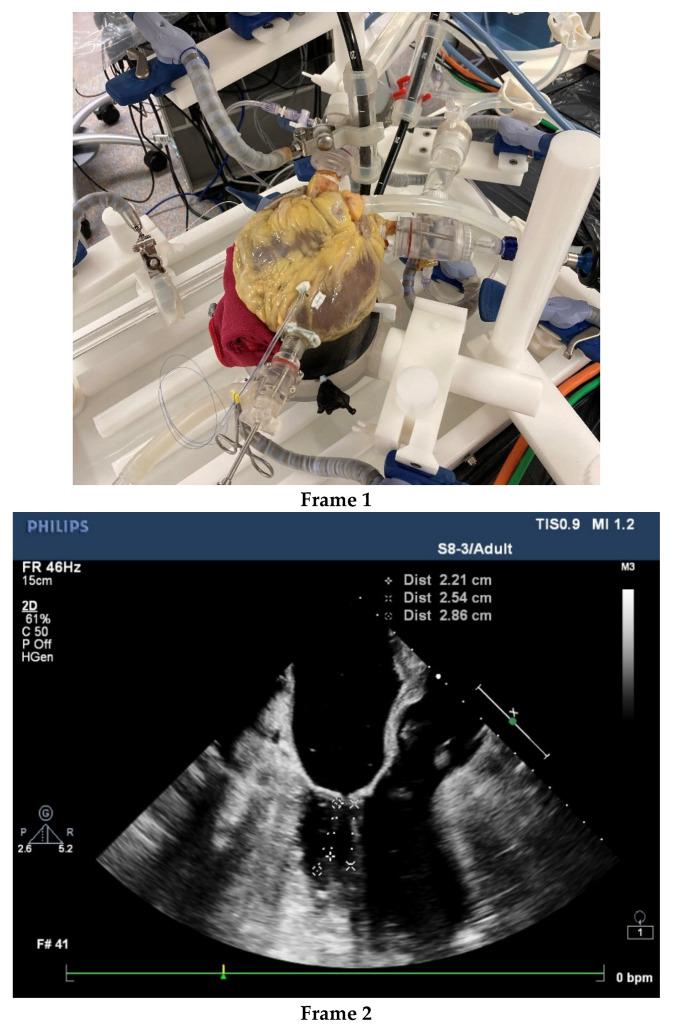

Almost 30 years after the first endoscopic mitral valve repair, Minimally Invasive Mitral Valve Surgery (MIMVS) has become the standard at many institutions due to optimal clinical results and fast recovery. The question that arises is can already good results be further improved by an Institutional Risk Management Performance (IRMP) system in decreasing risks in minimally invasive mitral valve surgery (MIMVS)? As of yet, there are no reports on IRMP and learning systems in the literature. (2) : We described and appraised our five-year single institutional experience with MIMVS in isolated valve surgery included in the Netherlands Heart Registry (NHR) and investigated root causes of high-impact complications. (3) : The 120-day and 12-month mortality were 1.1% and 1.9%, respectively, compared to the average of 4.3% and 5.3% reported in the NHR. The regurgitation rate was 1.4% compared to 5.2% nationwide. The few high-impact complications appeared not to be preventable. (4) : In MIMVS, freedom from major and minor complications is a strong indicator of an effective IRMP but remains concealed from physicians and patients, despite its relevance to shared decision making. Innovation adds to the complexity of MIMVS and challenges surgical competence. An IRMP system may detect and control new risks earlier. (5) : An IRMP system contributes to an effective reduction of risks, pain and discomfort; provides relevant input for shared decision making; and warrants the safe introduction of new technology. Crossroads conclusions: investment in machine learning and AI for an effective IRMP system is recommended and the roles for commanding and operating surgeons should be considered.